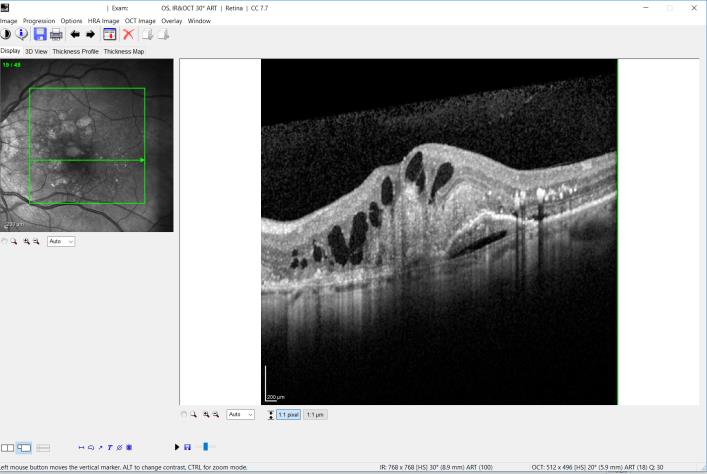

Απαραίτητη προϋπόθεση για τη διάγνωση της ΗΕΩ είναι η εξέταση του αμφιβληστροειδούς από τον οφθαλμίατρο στη σχισμοειδή λυχνία με τη βοήθεια ειδικών φακών που επιτρέπουν την εξέταση της ωχράς υπό μεγέθυνση (βυθοσκόπηση). Τη διάγνωση βοηθάει μια πολύ σημαντική εξέταση, η λεγόμενη φλουοροαγγειογραφία. Πρόκειται για λήψη φωτογραφιών του αμφιβληστροειδούς σε συγκεκριμένα ειδικά χρονικά σημεία, αφού εγχυθεί η χρωστική ουσία «φλουορεσεΐνη» ενδοφλεβίως. Την πραγματική επανάσταση τόσο στη διάγνωση όσο και στα follow up σε όλες τις νόσους της ωχράς (συμπεριλαμβανομένης της ΗΕΩ) έδωσε μια μοντέρνα εξέταση, που παρέχει τη δυνατότητα να εξεταστεί με απόλυτη ευκρίνεια και ακρίβεια η ωχρά κηλίδα. Η εξέταση αυτή καλείται OCT (οπτική τομογραφία συνοχής) και ανήκει στις «εκ των ων ουκ άνευ» εξετάσεις για την ωχρά, γιατί κάνει ορατές ακόμα και πολύ μικρές ποσότητες υγρού, άρα καθιστά εφικτή τη διάγνωση της νόσου ακόμα και σε πολύ αρχικά στάδια.

Εικόνα OCT ασθενούς με υγρή μορφή της ΗΕΩ